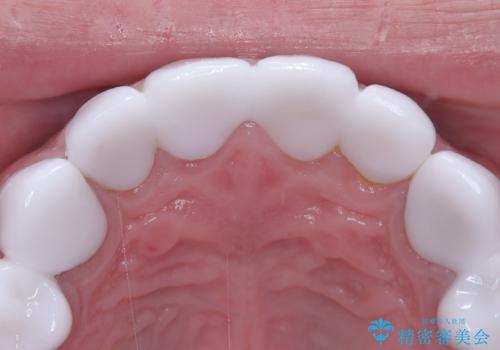

- 治療計画

治療では、まず古いクラウンを慎重に取り外し、歯肉の状態を整えました。その後、精密な型取りから患者様一人ひとりに合わせたオーダーメイドのオールセラミッククラウンを作製。金属を一切使用しないため、歯肉の変色を防ぎ、天然歯のような透明感と美しさを再現します。新しいクラウンは、歯肉のラインに合わせてぴったりと適合するよう調整し、見た目の違和感を解消。長年の悩みが解決し、自然で美しい口元と笑顔を取り戻していただけました。